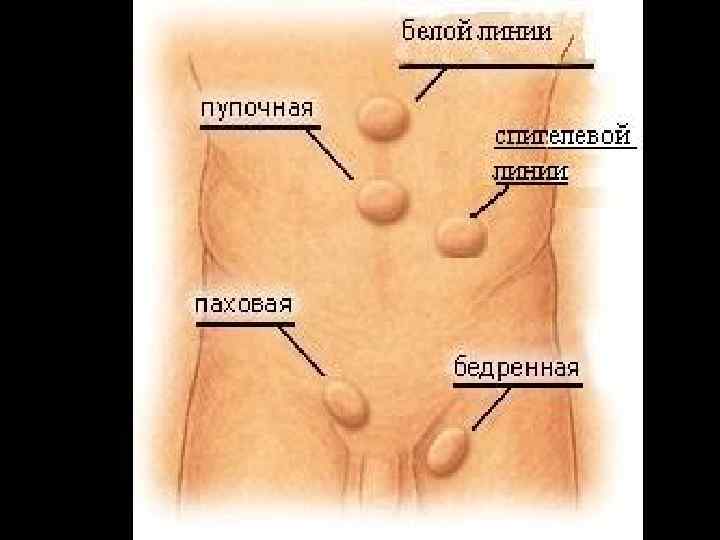

КЛАССИФИКАЦИЯ НАРУЖНЫХ БРЮШНЫХ ГРЫЖ По локализации • паховая • бедренная • пупочная • белой линии живота • в области послеоперационного рубца • редкие виды грыж

Грыжа спигелевой линии • Грыжи спигелевой линии — это грыжи брюшной стенки которые появляются вдоль субумбиликального участка спигелевой (полулунной) линии и через спигелеву фасцию.